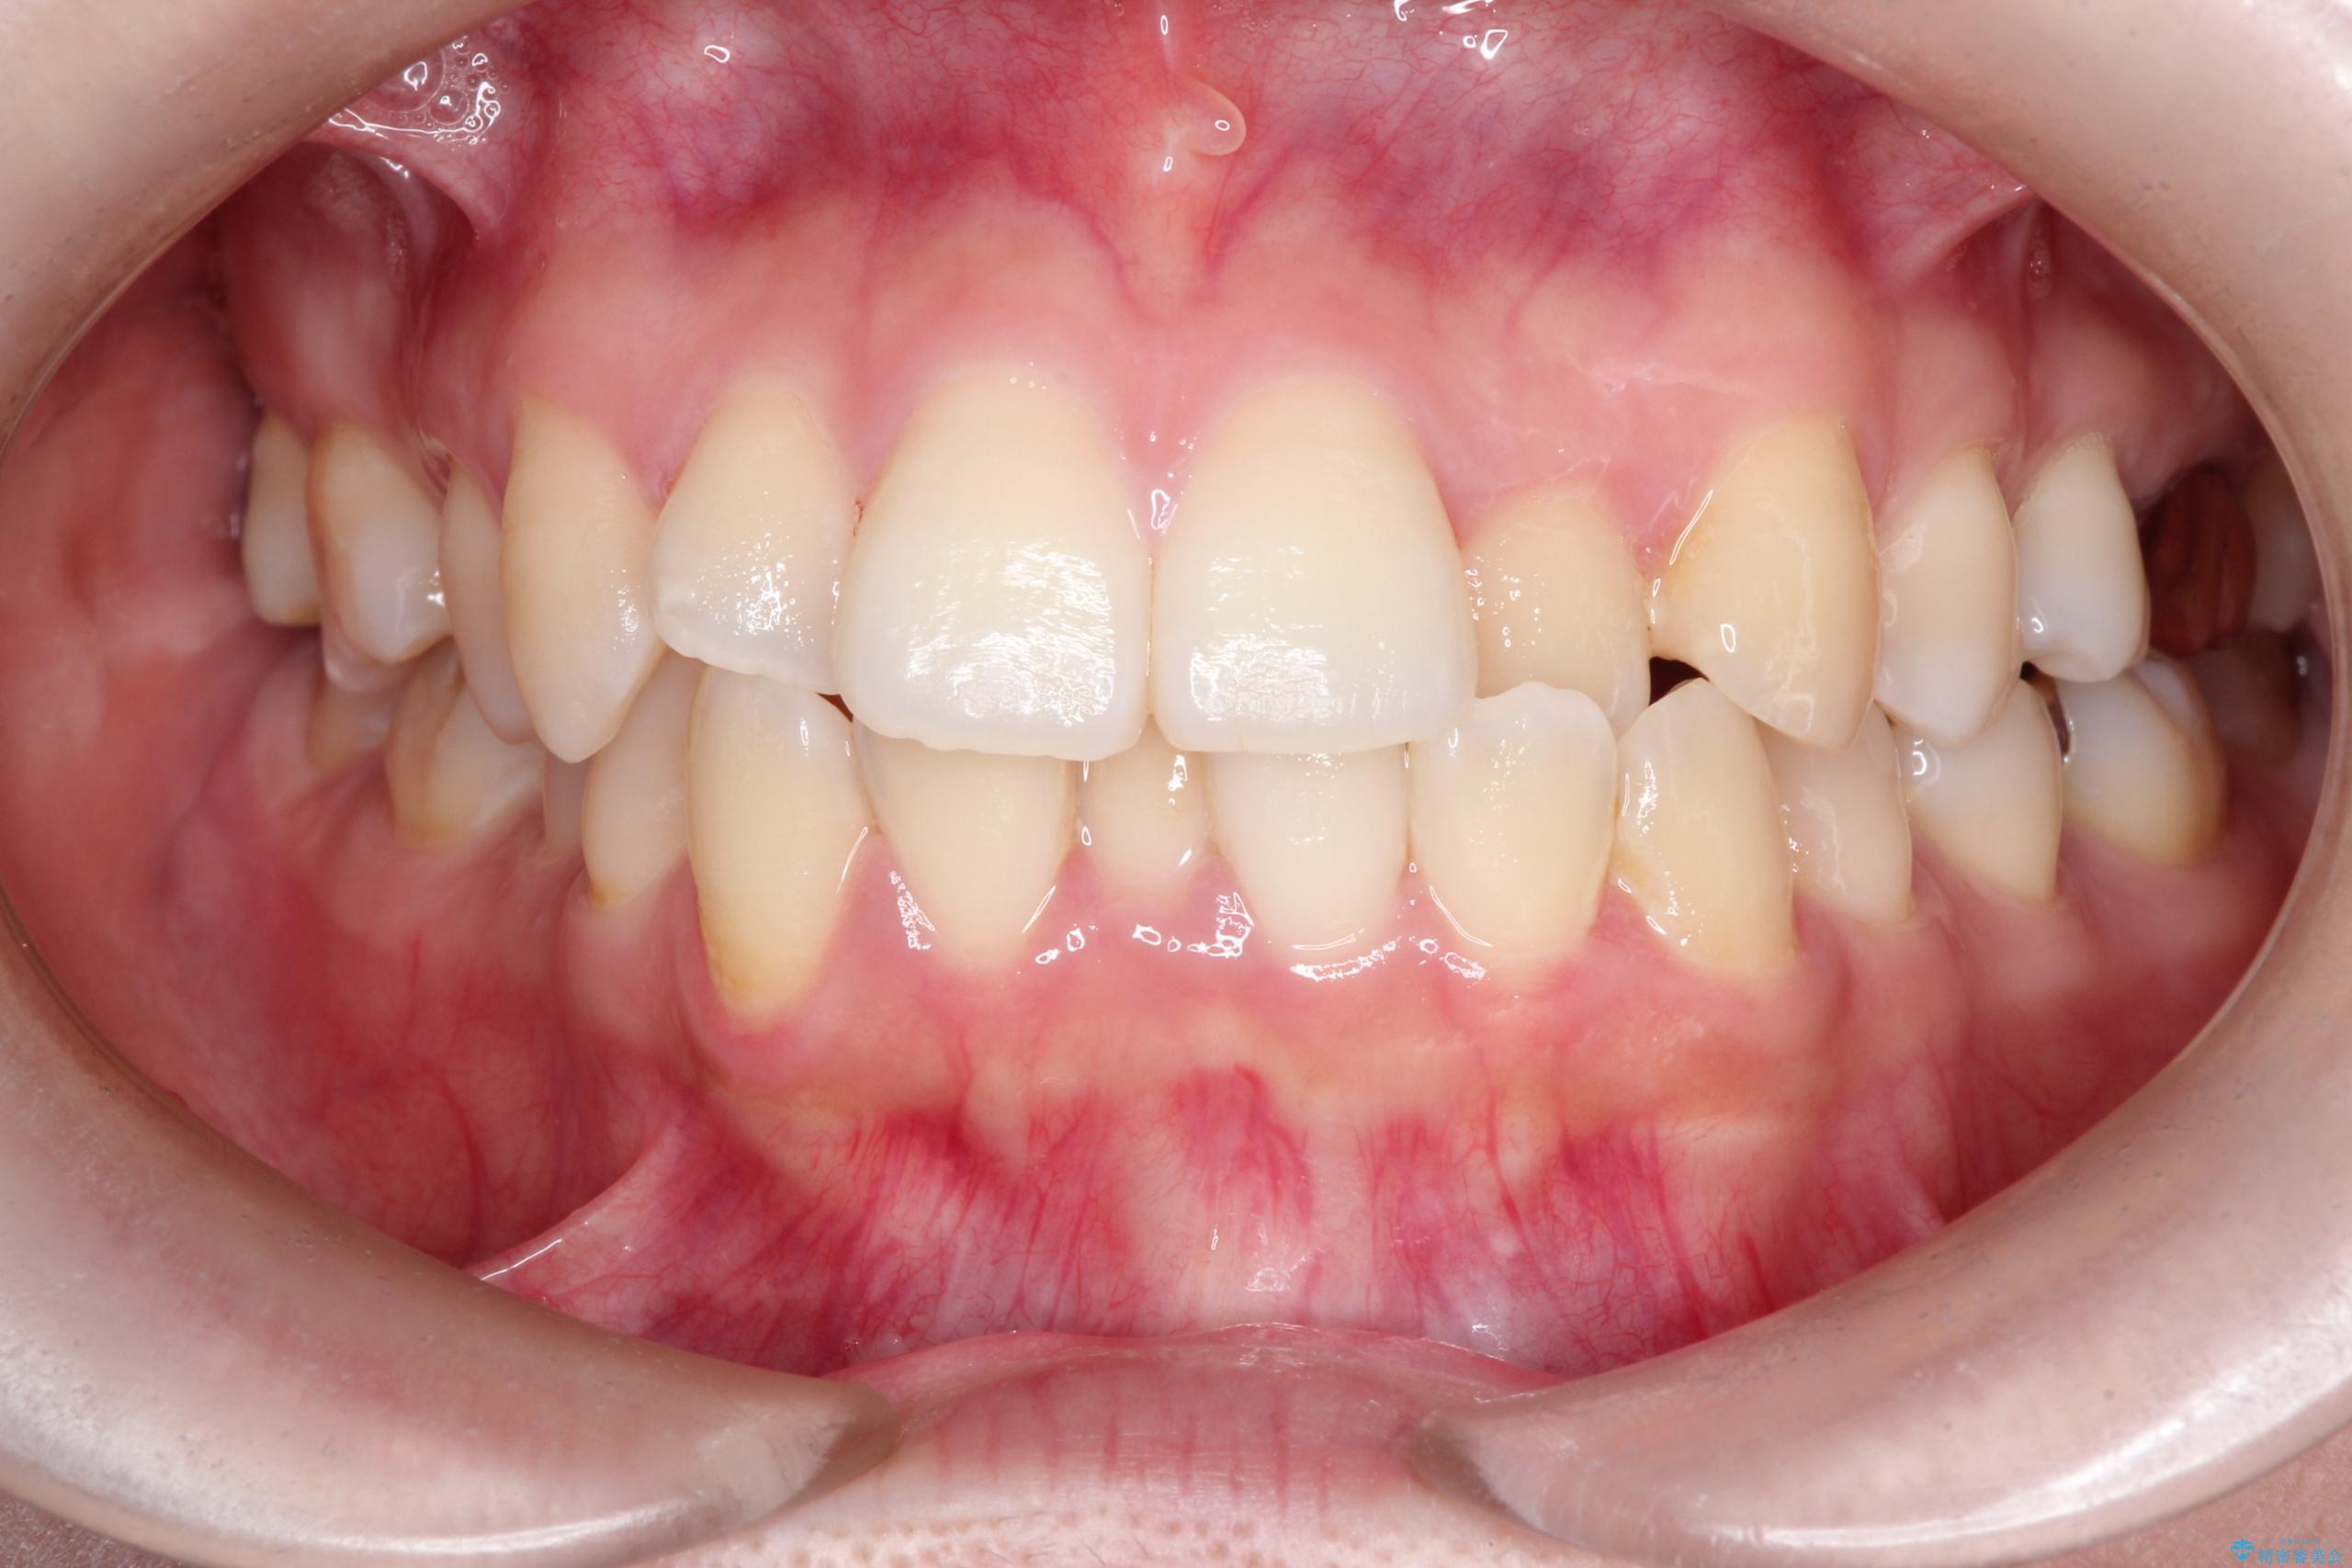

- 主訴:口元を下げて前突感を無くしたい、下の歯の凹凸も無くしたい

右側第二小臼歯、左側第一小臼歯、下顎両側第一大臼歯を抜歯しワイヤ-矯正を行いました。

骨格的顎の変位を認めたため、顔貌に対しピッタリ上下の歯の正中を合わせることは難しいと説明し、上下左右計4本小臼歯を抜歯しワイヤー矯正治療を行いました。